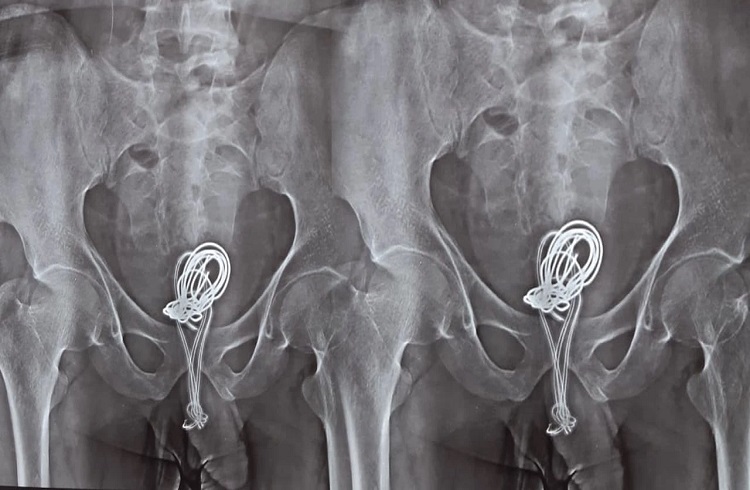

ಅವನ ನೋವನ್ನು ನೋಡಿ, ಅವನ ಕುಟುಂಬ ಸದಸ್ಯರು ಗೊಂದಲಕ್ಕೊಳಗಾದರು ಮತ್ತು ಅವನನ್ನು ಆಸ್ಪತ್ರೆಗೆ ಕರೆದೊಯ್ದರು. ಅಲ್ಲಿ ವೈದ್ಯರು ಪರೀಕ್ಷೆಗಳನ್ನು ನಡೆಸಿದಾಗ.. ಮೂತ್ರಕೋಶದಲ್ಲಿ ಚಾರ್ಜರ್ ಅನ್ನು ಕಂಡು ಅವರು ಆಶ್ಚರ್ಯಚಕಿತರಾದರು. ಆನ್ ಬಿನ್ಹ್ ಆಸ್ಪತ್ರೆಯ ವೈದ್ಯರು ಸುಮಾರು ಎರಡು ಗಂಟೆಗಳ ಕಾಲ ಶಸ್ತ್ರಚಿಕಿತ್ಸೆಯನ್ನು ತ್ವರಿತವಾಗಿ ಮಾಡಿ ಅದನ್ನು ತೆಗೆದುಹಾಕಿದರು. ಆರಂಭದಲ್ಲಿ, ವೈದ್ಯರು 30 ನಿಮಿಷಗಳ ಕಾಲ ಎಂಡೋಸ್ಕೋಪಿಕ್ ಶಸ್ತ್ರಚಿಕಿತ್ಸೆಯನ್ನು ಮುಂದುವರೆಸಿದರು.. ತಂತಿಯನ್ನು ದೇಹದೊಳಗೆ ಕುಣಿಕೆಗಳಲ್ಲಿ ಸುತ್ತಿಡಲಾಗಿತ್ತು.. ಕಾರ್ಯವಿಧಾನವು ಜಟಿಲವಾಯಿತು. ಇದಲ್ಲದೆ, ಮೂತ್ರಕೋಶದ ಒಂದು ಭಾಗವು ಅದರಿಂದ ಕೊಳೆಯುತ್ತಿದೆ ಎಂದು ವೈದ್ಯರು ಕಂಡುಕೊಂಡರು. ಆದರೆ, ಕೊನೆಗೆ ಶಸ್ತ್ರಚಿಕಿತ್ಸೆ ಮಾಡಿ ಅದನ್ನು ತೆಗೆದುಹಾಕಲಾಯಿತು. ಎರಡು ದಿನಗಳ ನಂತರ, ಹುಡುಗನಿಗೆ ಕೌನ್ಸೆಲಿಂಗ್ ನೀಡಿ ಕಳುಹಿಸಲಾಯಿತು.